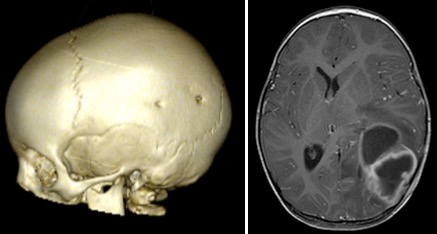

la fracture est-elle à risque ?

- de fracture évolutive si il existe :

- une brèche durale : quasi certaine si l’écart inter-fragmentaire est supérieur à 5 mm

- une contusion cérébrale sous-jacente